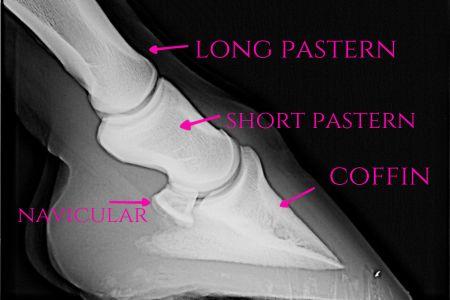

Here are some anatomy photos:

The hoof on the right has laminitis with rotation of the coffin bone. The hoof on the left is normal.